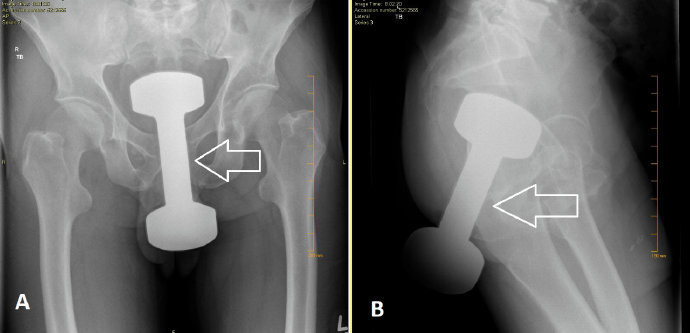

据统计,在急诊室中,男性“失物招领”的情况是女性的40倍,大部分失物是在肠道中被发现的,而且花样繁多……